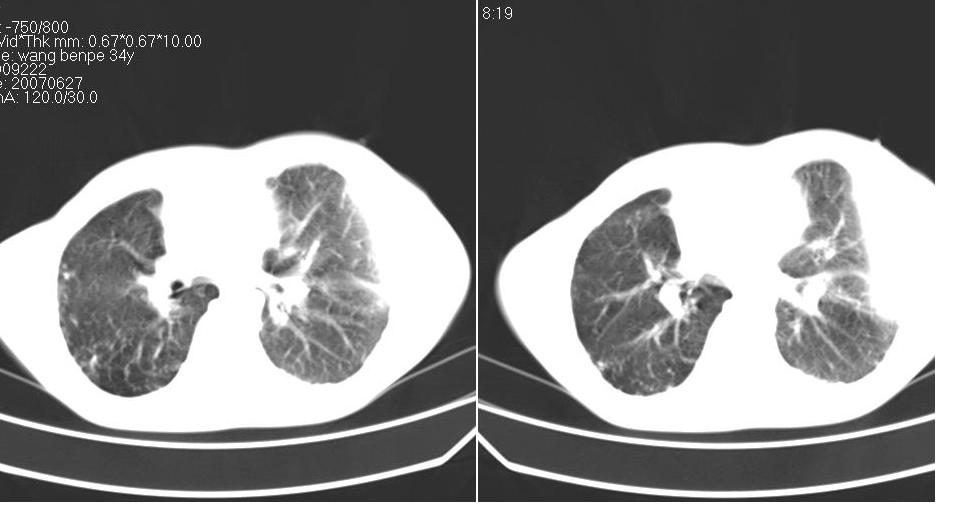

以下是引用苯小孩在2007-6-27 15:09:00的发言:[br]考虑:1、右肺继发性肺结核.2、双侧包裹性积液<胸腔及叶间>3、双侧局部胸膜增厚.[br]建议胸水化验检查.

以下是引用yanghaochen88在2007-6-27 15:08:00的发言:[br]双肺上野散在粟粒状影、包裹性积液、胸膜增厚粘连、叶间积液---tb,至于分型还得结合病史体征细究妥当些。

以下是引用zjzjr在2007-6-27 16:49:00的发言:[br]肺结核、结核性胸膜炎。